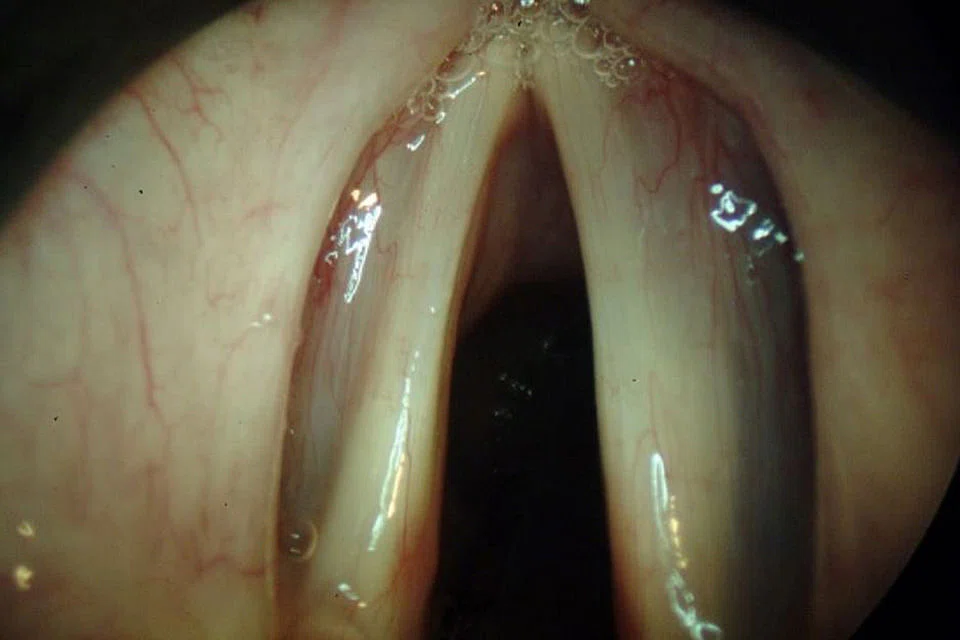

The "gold" standard for voice evaluation using endoscopes is a videolaryngostroboscopy (VLS). This examination is performed usually without any need for anaesthesia, takes a few minutes at most and allows for visualisation of the movement of the vocal folds and their mucosal wave. Current technology has improved to an extent that the digital camera is at the tip of the flexible scope with high-definition image capture.

Surgical intervention for the ageing voice is rarely recommended in isolation. Most patients benefit from SALT before and after surgery. The aim of surgery in the ageing larynx, assuming that there are no other vocal fold pathologies (nodule, polyps, cysts) is to provide a better bulk to the atrophy of the folds.

This involves injecting bio-compatible materials either in the office setting with the patient awake or in the operating theatre under a general anaesthetic (see images 1 and 2).

Surgery does not however restore the loss of the SLP and the pliability of the folds does not improve. It does however help improve voice quality and amplification.